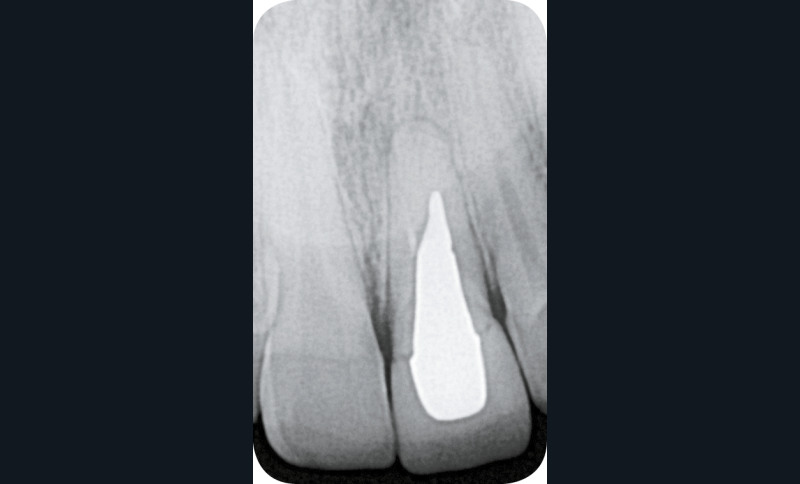

L’examen clinique révèle la présence d’un biotype parodontal épais, une gêne lors de la palpation vestibulaire ainsi qu’une douleur à la percussion. La réalisation d’une radiographie rétro-alvéolaire et d’un CBCT confirme la présence d’une fissure radiculaire (fig. 2).

Avec l’aide du prothésiste, le fichier DICOM du CBCT et le fichier issu de l’empreinte optique sont associés. Afin de simuler au mieux la situation endo-buccale de la patiente, l’extraction virtuelle de la 21 est effectuée.

Cette visualisation de l’avulsion permet dans un second temps le positionnement dans cette même zone d’un implant (de plateforme standard 4,20 x 13) grâce à un logiciel de planification implantaire…